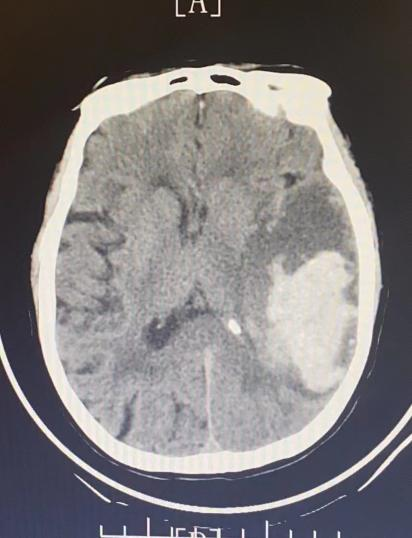

主訴:女性患者,77歲,因突發(fā)意識不清伴嘔吐2小時急送入院。

既往史:有高血壓病史多年、曾行腰椎間盤手術。

查體: GCS評分10分,神志模糊,右側瞳孔1.5mm,對光反應存在,左側瞳孔1.5mm,對光反應存在,左側肢體肌力5級,右側肢體肌力3級。

圖片

手術前

患者行神經(jīng)內(nèi)鏡下腦出血清除術,術后瞳孔等大等圓,對光反應存在。術后第1天患者神志清楚,四肢能活動,肌力正常。

手術后